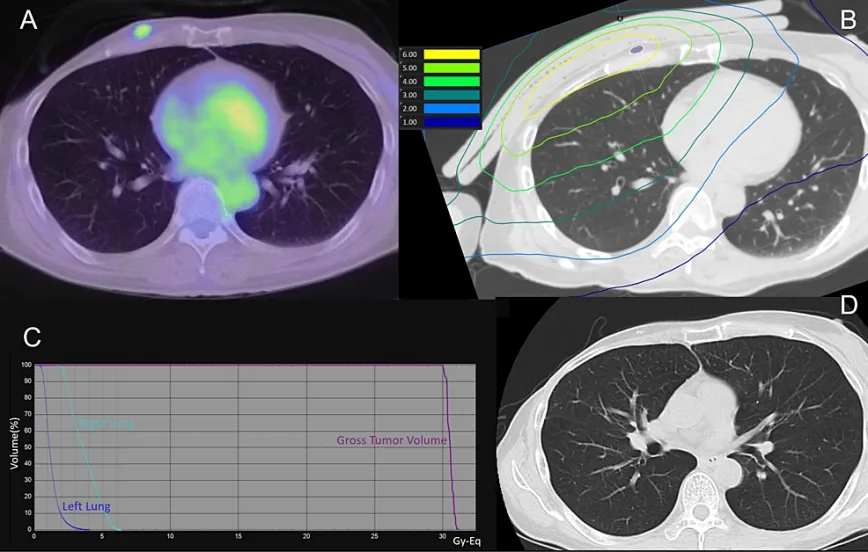

該患者因右側(cè)乳腺癌接受化療,隨后行保乳手術(shù),并在10年間進(jìn)行了25次總劑量為50Gy的保乳放療。3年前,患者因局部復(fù)發(fā)進(jìn)行了手術(shù)和化療,盡管先后進(jìn)行了兩次手術(shù)干預(yù)和激素治療,癌癥還是再次復(fù)發(fā),最終開始了BNCT治療。處方劑量最低為30Gy-Eq,同側(cè)肺平均劑量為3.7Gy-Eq。BNCT后第1、7、30、60和90天的CT掃描結(jié)果均未顯示放射性肺炎的證據(jù)。圖3為患者治療90天后的肺部劑量分布和CT掃描結(jié)果。

(A)治療前PET-CT。

(B) BNCT(肺)劑量分布圖。紫色表示腫瘤總體積

(C)劑量-體積直方圖

(D)治療后90天的CT掃描顯示腫瘤總體積縮小